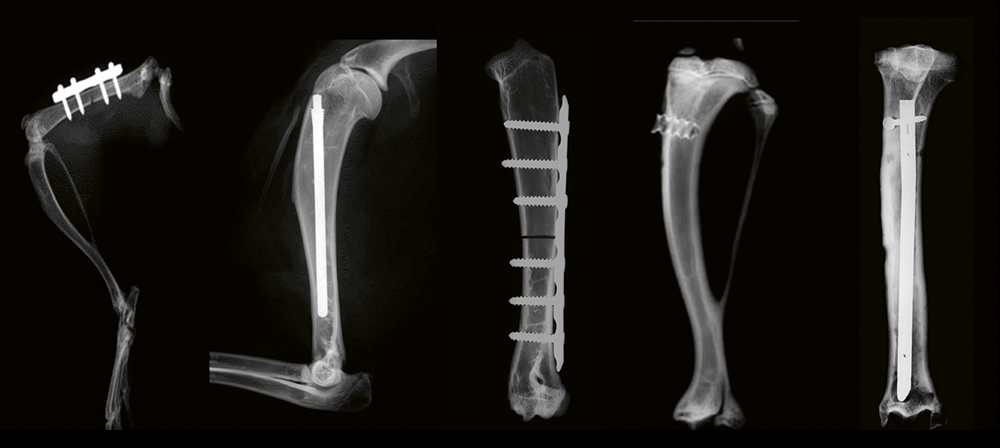

In vivo models of infection at ARI, l-r: mouse femoral plate, rabbit humeral nail, rabbit humeral LCP, rat tibial screw, sheep tibial nail